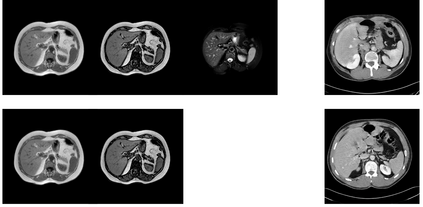

In many clinical settings, the use of both Computed Tomography (CT) and Magnetic Resonance (MRI) is necessary to pursue a thorough understanding of the patient's anatomy and to plan a suitable therapeutical strategy; this is often the case in MRI-based radiotherapy, where CT is always necessary to prepare the dose delivery, as it provides the essential information about the radiation absorption properties of the tissues. Sometimes, MRI is preferred to contour the target volumes. However, this approach is often not the most efficient, as it is more expensive, time-consuming and, most importantly, stressful for the patients. To overcome this issue, in this work, we analyse the capabilities of different configurations of Deep Learning models to generate synthetic CT scans from MRI, leveraging the power of Generative Adversarial Networks (GANs) and, in particular, the CycleGAN architecture, capable of working in an unsupervised manner and without paired images, which were not available. Several CycleGAN models were trained unsupervised to generate CT scans from different MRI modalities with and without contrast agents. To overcome the problem of not having a ground truth, distribution-based metrics were used to assess the model's performance quantitatively, together with a qualitative evaluation where physicians were asked to differentiate between real and synthetic images to understand how realistic the generated images were. The results show how, depending on the input modalities, the models can have very different performances; however, models with the best quantitative results, according to the distribution-based metrics used, can generate very difficult images to distinguish from the real ones, even for physicians, demonstrating the approach's potential.